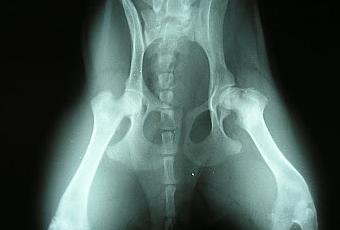

La malattia di Legg - Perthes Calve’ e'una patologia della testa del femore causata da una carenza dell'afflusso del sangue alla testa del femore durante l'età dello sviluppo, a causa di questa alterata irrorazione l'osso "muore" dando come risultato perdita di tessuto osseo con conseguente collasso della struttura ossea del collo e testa del femore che si deforma appiattendosi. La patologia riscontrata tra i cinque e gli otto mesi di età , le razze maggiormente colpite sono quelle toy , si manifesta all’inizio con una lieve zoppia con il progredire della malattia il cane sottrae l’arto al carico per il dolore intenso.

Una volta confermata la diagnosi di LPD il trattamento è di tipo chirurgico e consiste nel rimuovere la testa del femore danneggiata (osteoctomia della testa del femore).